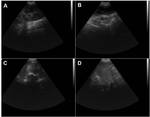

La figura 2 correspondiente a las imágenes del examen ecográfico abdominal que muestra al explorar la glándula mamaria lesiones compatibles con carcinoma sin evidencia de condición metastásica. Se reporta la presencia de masas heterogéneas de estructura irregular con áreas hipoecoicas e hiperecoicas con bordes mal definidos, vascularización aumentada, microcalcificaciones y áreas anecoicas dentro del tumor debido a degradación tisular. No se observa invasión local con extensión a tejidos adyacentes o alteración de los ganglios linfáticos regionales.

Figura 2. Imágenes de ecografía abdominal de un canino hembra Husky Siberiano de 10 años de edad. (A) Riñón izquierdo, (B) glándula mamaria, (C) glándula mamaria, (D) bazo.

El estudio ecográfico del caso clínico analizado en este trabajo, muestra lesiones compatibles con carcinomas, reportándose la presencia de masas heterogéneas de estructura irregular con áreas hipoecoicas e hiperecoicas con bordes mal definidos, vascularización aumentada, microcalcificaciones y áreas anecoicas dentro del tumor debido a degradación tisular, lo que se correlaciona con el carcinoma de tipo complejo identificado por medio del análisis histológico.